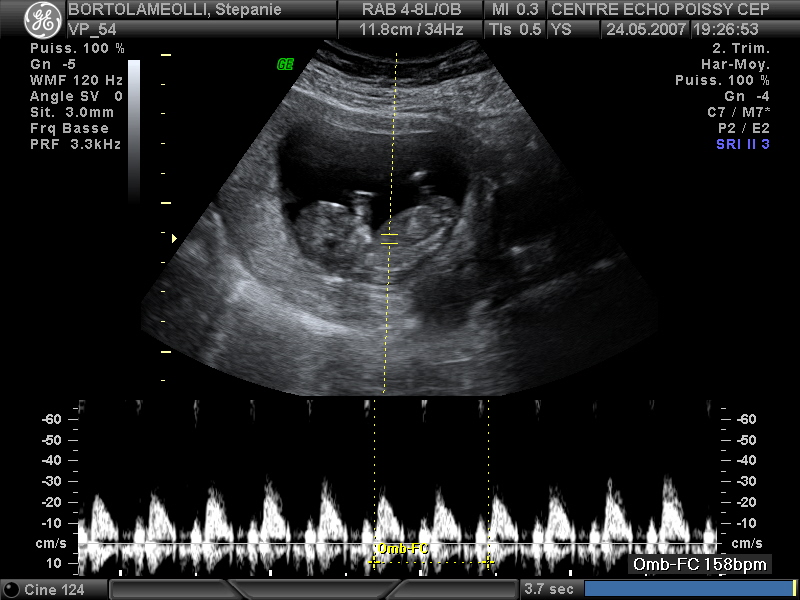

Echographies

Mai 2007